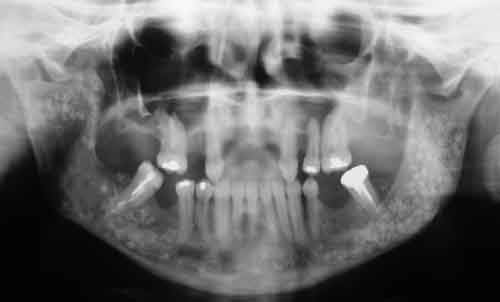

Femme de 40 ans. Aucun antécédent (notamment chirurgical) en dehors d'un DNID, d'un tabagisme modéré (5 paquets-année) et d'une surcharge pondérale. Consulte pour apparition progressive d'une volumineuse voussure dans les 2 vestibles inférieurs et d'une modification consécutive de la forme de la partie inférieure de son visage. A l'examen clinique : tuméfaction dure et fixée dans les 2 vestibules. Sensibilité (V3) normale. Gencive normale. Dents restantes non mobiles, vitales. Pas d'adénopathies palpables. Biologie non faite pour l'instant. Je vous joinds l'OTP et le scan. Diagnostic et options de traitement?

du coté de la dent incluse dans le ramus, on peut penser comme diagnostic probable a un kyste d'origine dentaire -image uniloculaire bordée sur son pourtour par une corticale bien individualisée et sur le scanner disparition de l'espace péricoronaire de la couronne avec continuité de toute la cavité.

diagnostic différentiel a faire avec d'autre lésions par ponction et anapat qui confirmeront ou non le diagnostic présomptif.

traitement suivant le diagnoctic de l'autre coté ou

on a le choix entre pas mal de choses dont l'ameloblastome, le kyste multiloculaire, le kyste dentigère, la tumeur de Pindborg

alors?

je ne pense pas a l'ameloblastome, on n'a pas ici l'image caracteristique en "bulles de savon",on n'a pas de projection de petites cavités radioclaires en périphérie et pas de resorption des dents adjacentes qui restent vitales

le kyste multiloculaire montre plusieurs compartiments bien définis , ici l'origine dentaire est possible mais n'explique pas les images multiples derriere la molaire donc peu probable

on peut penser a une tumeur de Pindborg, les pourtours des cavités sont moins nettes et rondes que pour un améloblastome et de plus la tumeur a des bords irréguliers et une tendance à l'envahissement local qui semble confirmé par la disparition de la corticale supérieure sur la partie coronaire de la mandibule

au final l'absence de douleurs et de signes de douleurs des dents par compression ou lesion du V3 laisse espérer le caractère local de la lésion.

Bref, en ce qui concerne ce cas (assez récent), je vous livre le raisonnement qui a été le notre : probables kystes péricoronnaires sur les dents incluses (il n'y a pas de dents "surnuméraires"...). Décision d'abord chirurgical pour énucléation des 3 kystes (les ponctions ne "marchent" pas dans ces lésions) et examens anatomopathologiques extemporanés pour décider, en per-opératoire, de la conduite à tenir (photo 1).